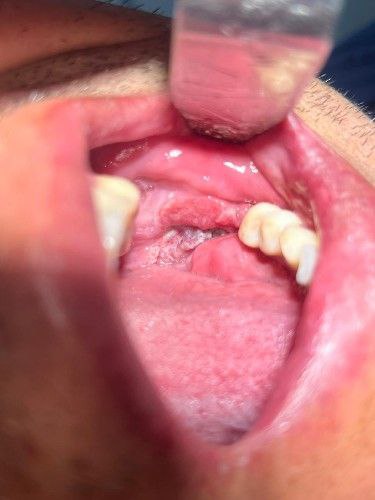

El cáncer de la cavidad bucal representa un gran desafío de supervivencia para la población Boliviana.

En el Centro Maxilofacial, combinamos más de 25 años de experiencia, tratamientos de vanguardia y con la bendición de Dios, trabajamos para devolver la esperanza y la calidad de vida a los pacientes que enfrentan esta enfermedad.

Contamos con la capacidad, la experiencia y el compromiso necesarios para el diagnóstico y tratamiento integral del cáncer bucal.